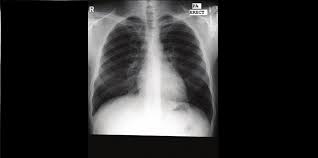

Paru paru berair berlaku apabila terdapat pengumpulan cecair yang berlebihan di dalam paru paru.

Paru paru berair yang tidak segera ditangani akan menyebabkan penderita mengalami gangguan pernafasan dinding paru paru yang bocor dan berbagai komplikasi berbahaya lainnya seperti kematian mendadak. Askum betul ke penyakit ni boleh menyebabkan kematian. Tak dinafikan pneumonia atau paru paru berair adalah antara penyakit yang menjadi punca utama yang menyebabkan hospitalization.

Rawatan bergantung pada punca tetapi selalunya melibatkan pemberian oksigen dan ubat ubatan. Muh ashury february 28th 2010 20 41. Terdapat beberapa faktor yang boleh menyebabkan paru paru berair.

Keadaan fungsi paru paru yang tiba tiba bertambah teruk dikenali sebagai kemerosotan akut boleh menjejaskan keadaan pesakit dan sering menyebabkan kematian dalam tempoh beberapa bulan. Badan anda bertarung untuk mendapatkan oksigen. Paru paru berair adalah salah satu penyakit yang terjadi pada saluran pernafasan yang tidak boleh dibiarkan tanpa pengobatan tepat.